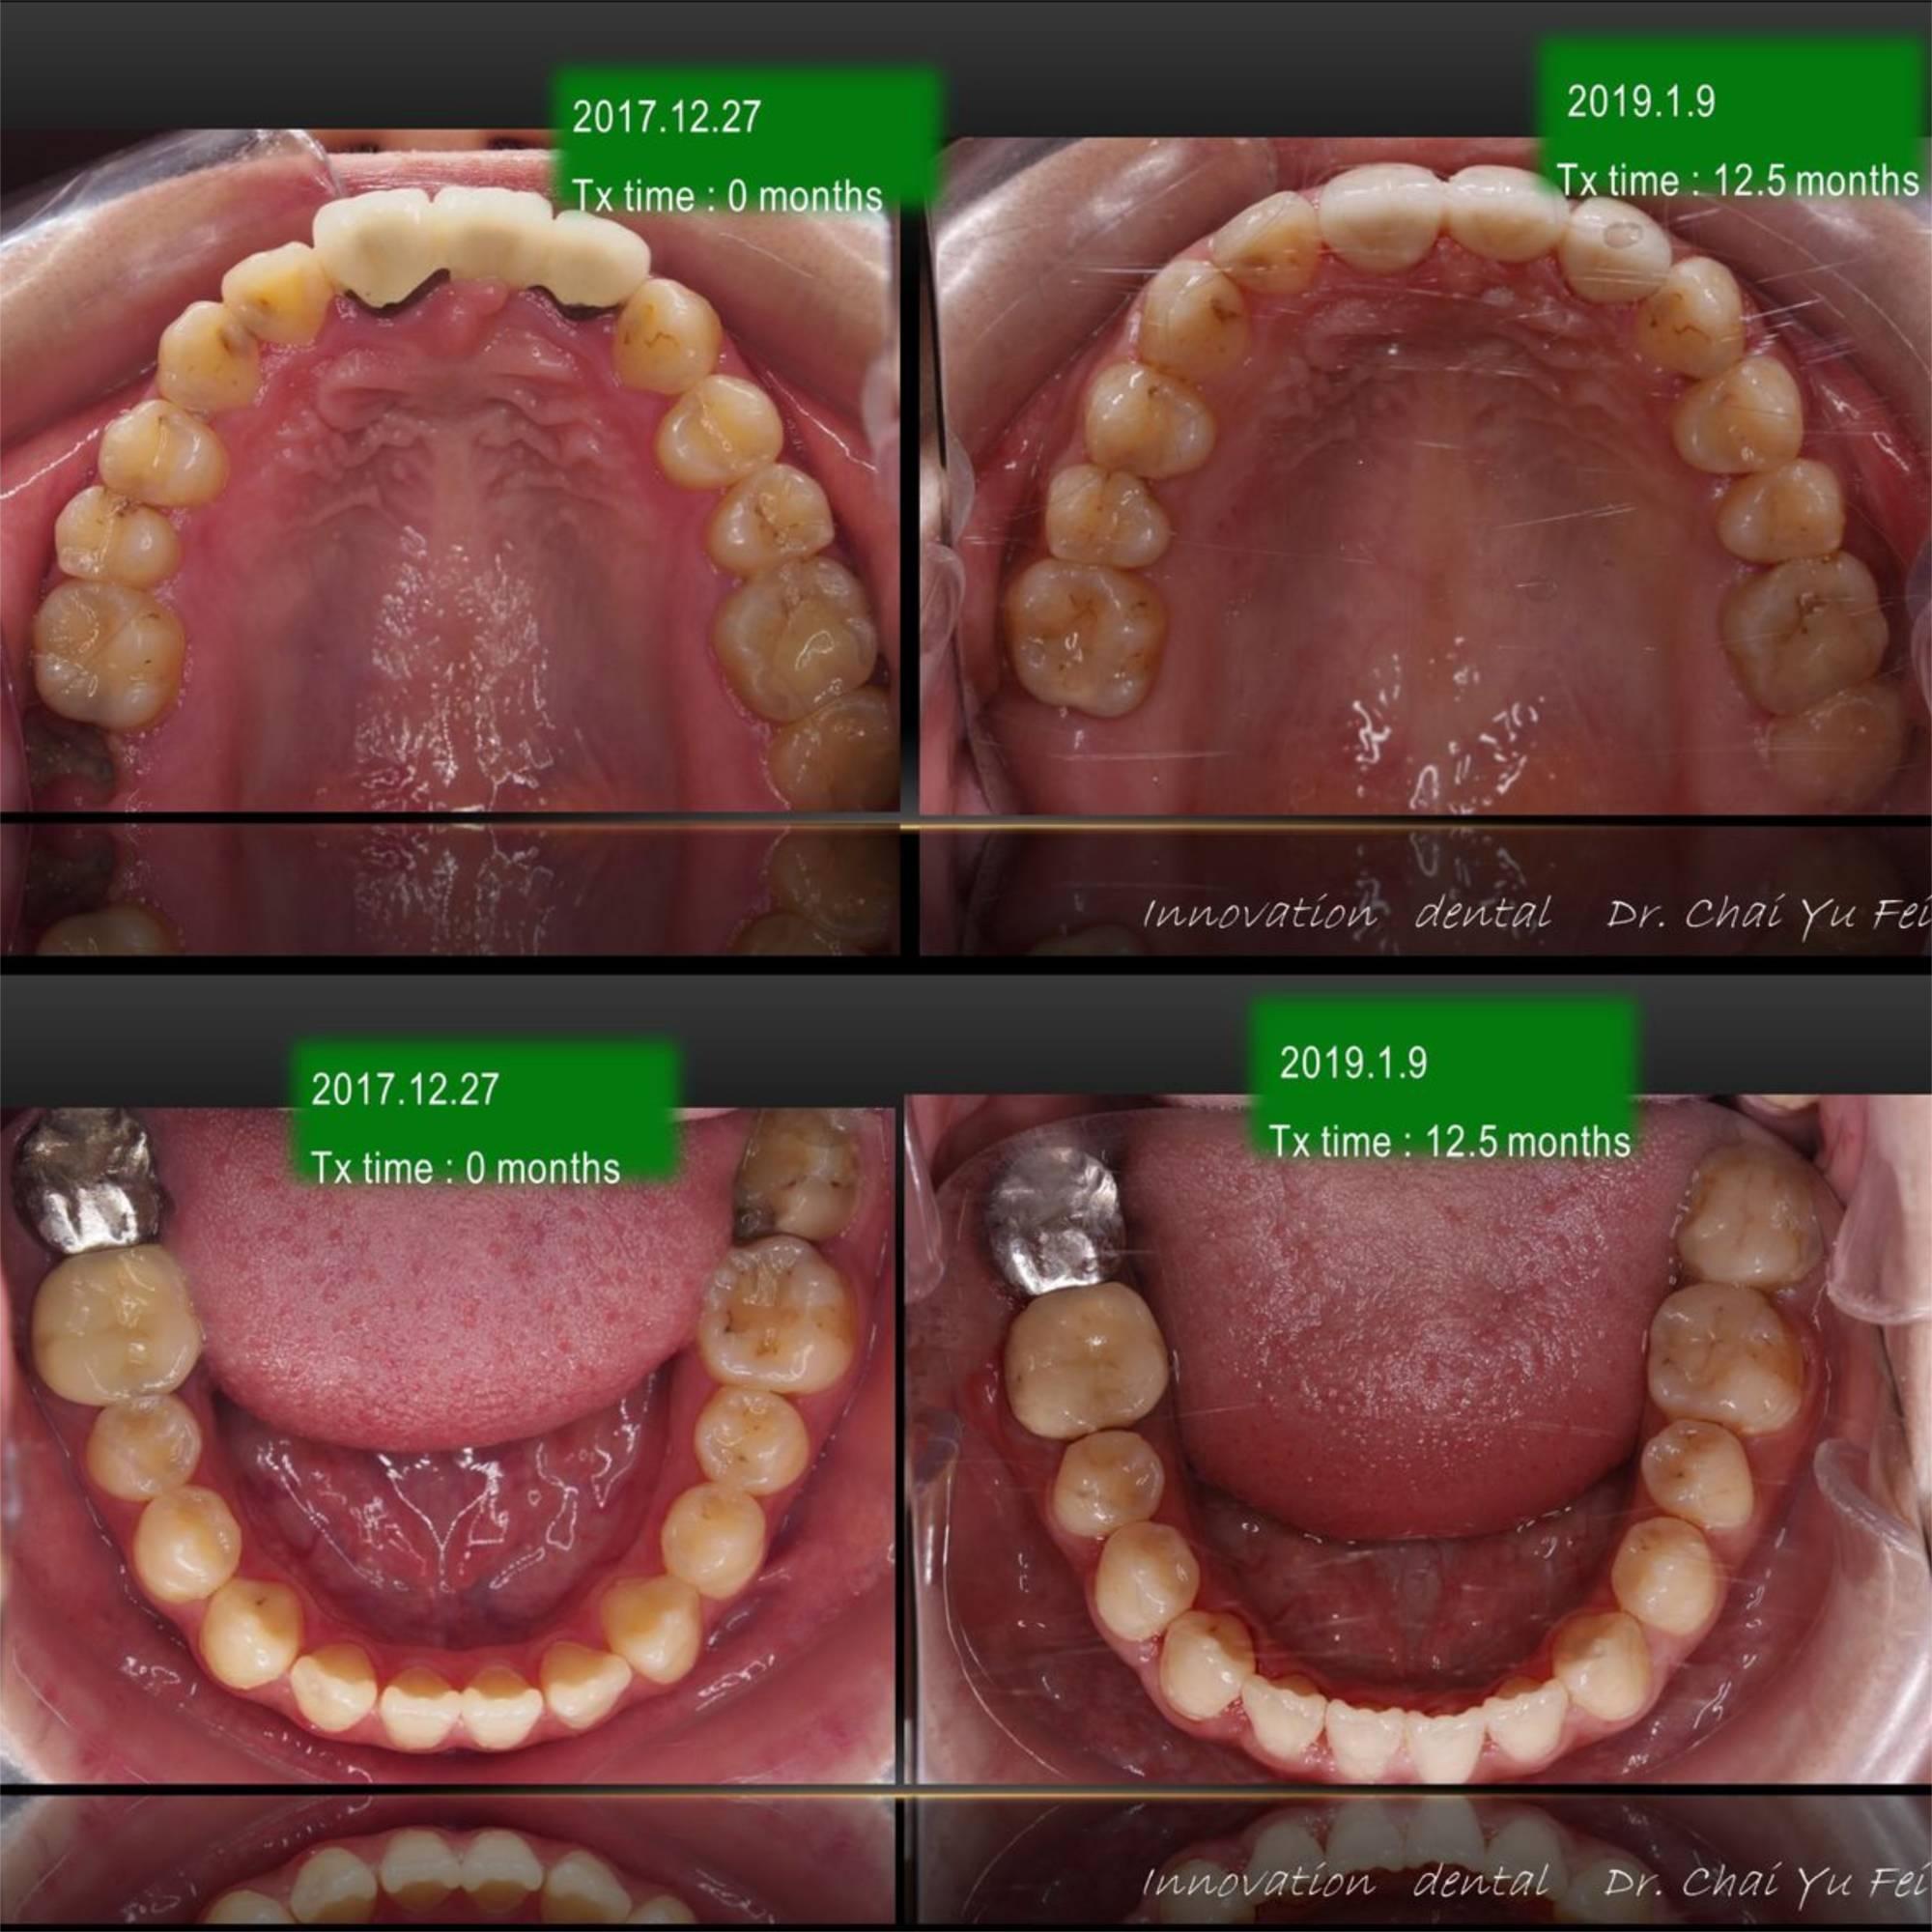

[ 治療時間 ] : 12.5 個月

[ 矯正器種類 ] : Roth 18X25 Slot 金屬零度矯正器

讓我們來看看她術前術後的成果吧~

下顎咬合平面打平,藉由手術後退達到理想咬合。